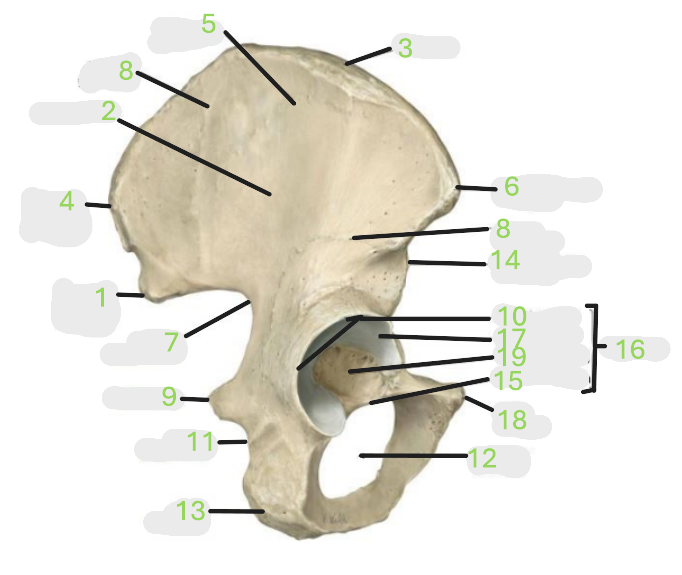

Where is the posterior inferior iliac spine

1

Where is the gluteal surface

2

Where is the iliac crest

3

Where is the posterior superior iliac spine

4

Where is the anterior gluteal line

5

Where is the anterior superior iliac spine

6

Where is the greater sciatic notch

7

Where is the inferior gluteal line

8

Where is the ischial spine

9

Where is the acetabular rim

10

Where is the lesser sciatic notch

11

Where is the obturator foramen

12

Where is the ischial tuberosity

13

Where is the anterior inferior iliac spine

14

Where is the acetabular notch

15

Where is the acetabulum

16

Where is the lunate surface

17

Where is the pubic tubercle

18

Where is the acetabular fossa

19